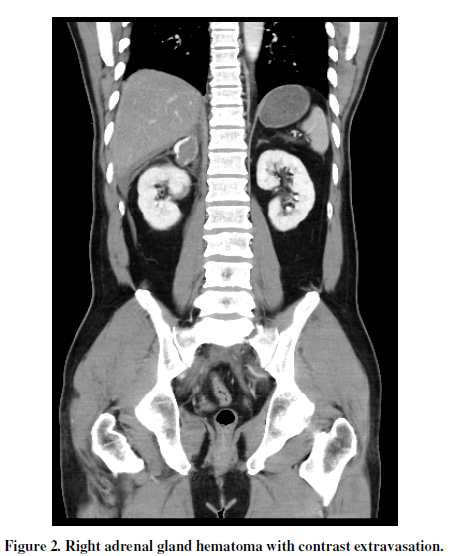

The 44-year-old male with hypertension and diabetic presented in the emergency department with torso pain after motor vehicle crash 30 minutes ago. The pain was located at right upper quadrant, flank, chest and back. Vital signs were stable. The sonography showed ascites over Morison’s pouch. The laboratory data showed GOT of 462 U/L and GPT of 497 U/L. The results of contrast-enhanced computed tomography (CT) were as following: (1) right adrenal gland hematoma with contrast extravasation(Figure 1, Figure 2), (2) liver laceration Grade II (Figure 1),(3) pelvic fracture (Figure 3). He received conservative treatment and discharged smoothly 20 days later.

Traumatic adrenal injury is a relative rare event which is reported in 0.15 to 4% of the blunt abdominal trauma cases[1]. Adrenal trauma is unilateral in 75–90 % of cases and most commonly affects the right adrenal gland [2]. The clinical management of adrenal trauma is usually directed by concomitant injuries, while the adrenal trauma itself is most often managed conservatively [3]. In addition, the most common CT manifestation of adrenal trauma is 2–3-cm oval hematoma [2]. Finally, the adrenal injury is an important indicator of the severity of trauma and associated with increased morbidity and mortality [2], such as in this case.